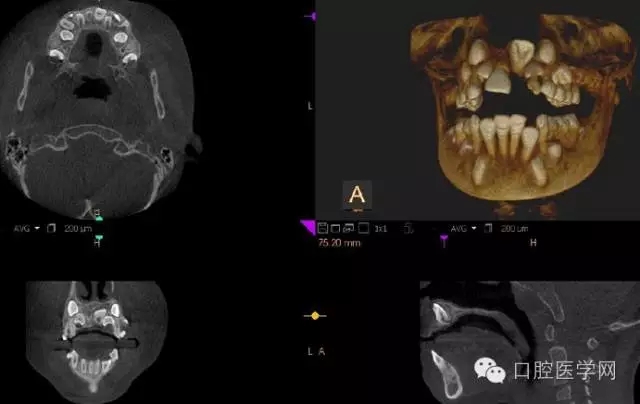

4.阻生牙

最常見于下頜第三磨牙

X線表現(xiàn):確定阻生牙的位置;確定阻生方向;牙根數(shù)目和形態(tài);阻生牙有無齲齒和根尖情況;與第二磨牙的關(guān)系;與下頜管的距離和磨牙后間隙的大小。